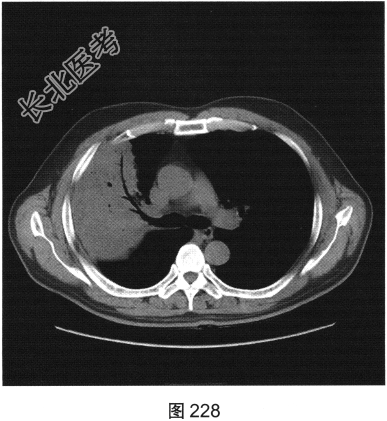

- [材料题] 患者男性,30岁。受凉后出现寒战、高热、咳嗽1天来医院就诊,听诊右上肺呼吸音减低。

- 简答题2、患者行胸部CT检查,如图227、图228所示。请问患者胸部CT可见哪些影像学表现?